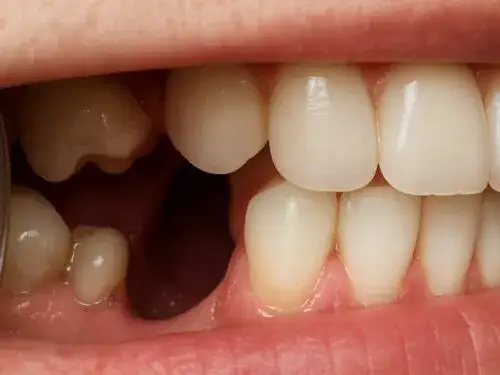

- Skaling: Jest to zabieg polegający na usunięciu kamienia nazębnego, czyli zmineralizowanej płytki bakteryjnej, która gromadzi się na zębach, zwłaszcza w miejscach trudno dostępnych dla szczoteczki. Kamień nazębny jest główną przyczyną chorób dziąseł i przyzębia.

Zaleca się, aby profesjonalne zabiegi higienizacyjne były wykonywane regularnie, zazwyczaj raz lub dwa razy w roku, w zależności od indywidualnych potrzeb i predyspozycji pacjenta. Wizyty kontrolne u stomatologa w tym samym czasie pozwalają na wczesne wykrycie wszelkich nieprawidłowości, takich jak początki próchnicy, choroby dziąseł czy zmiany na błonie śluzowej. Wczesne diagnozowanie i zapobieganie problemom jest zawsze bardziej efektywne, mniej bolesne i zazwyczaj tańsze niż leczenie zaawansowanych schorzeń.